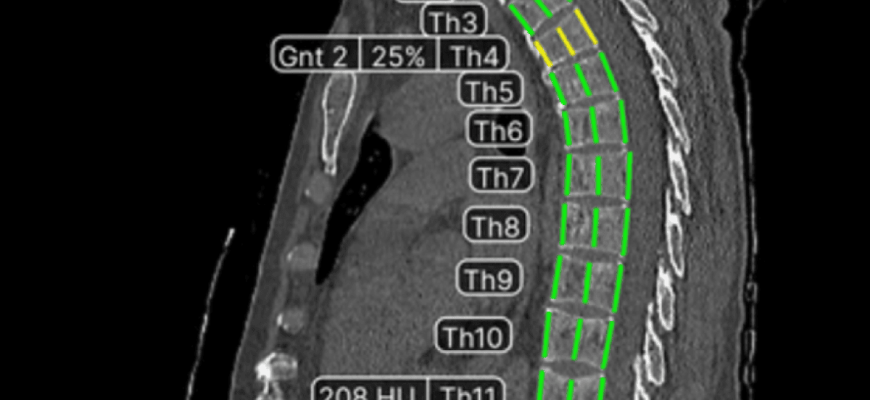

ИИ в гастроэнтерологии: Как анализ КТ меняет правила игры Привет‚ друзья! Сегодня мы окунемся в захватывающий мир гастроэнтерологии и посмотрим‚

Прекрасно! Приступим к созданию статьи. ИИ в гастроэнтерологии: Как алгоритмы видят то‚ что упускает глаз врача Мы живем в эпоху‚